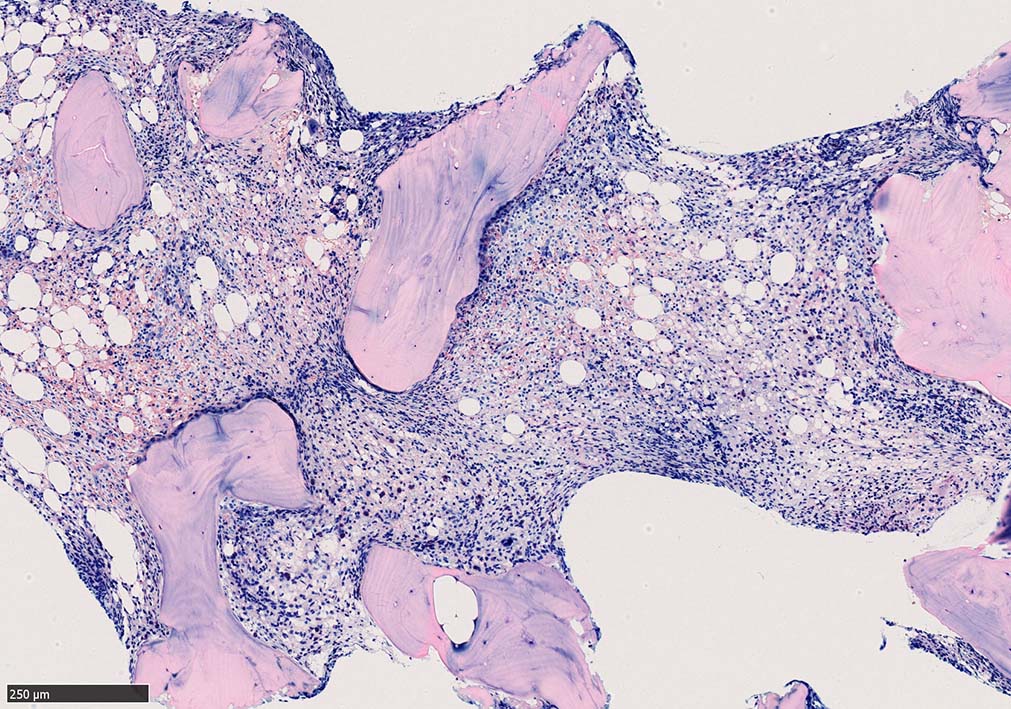

骨髄生検

bone marrow trephine biopsy: dry tapのため骨髄生検が行われる. cellularityは40-80%とhypercellular marrow. 流れのある細胞配列は線維化を疑わせる.

ASD-G 低倍率所見では赤芽球血島は幼若赤芽球の集簇巣が散在する, 顆粒球系細胞(ASDに赤く染色される)は減少,granulopoietic hypoplasiaを呈する.疎な集簇を示すmast cellsの増加がある.

ASD-G陰性の細胞がびまん性に増加しているように見える.

ASD-Giemsa陰性の細胞がシート状に増殖する. 核はクロマチン濃染, 核小体は不明瞭.類円形, 卵円形, くびれを持つ多稜形核, 長円形いびつで屈曲した核, など多彩. 細胞質は淡清色調, 広く淡明. 赤芽球血島は幼若赤芽球のみで形成される異形成像を示す. やや離れて成熟赤芽球が疎な集簇を示す.

Ag染色では, 疎な弾性線維が増生し,増殖細胞を小胞巣状に分画するいわゆる「lymphomatoid pattern」を呈する. 本例では, Mgkに異形成所見がある.